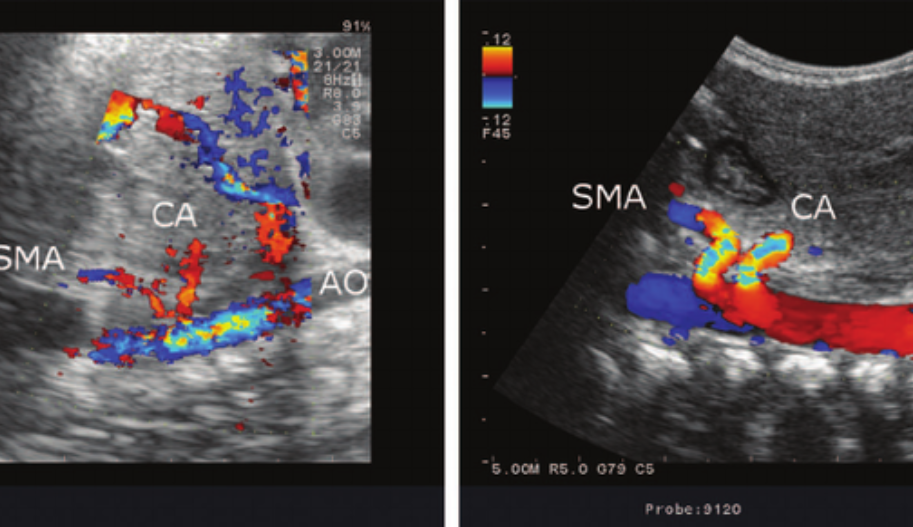

Celiac Trunk Color Doppler Ultrasound

The color Doppler ultrasound examination of the celiac artery typically begins with a transverse scan of the proximal abdominal aorta. The transverse approach often shows the bifurcation of the hepatic and splenic branches, resembling a “T” or a “seagull” appearance. For evaluating the origin of the celiac artery, a longitudinal approach is preferred. This view also allows for the evaluation of the SMA, which lies just below the celiac artery.